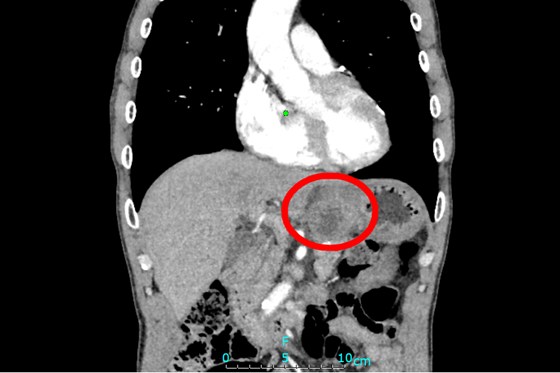

近日,湘雅常德医院普外科廖国庆教授团队成功开展一例多脏器联合切除术,一次性切除近端胃、胰体尾及脾脏,并用“双通道法”为患者重新建立消化系统,解除病灶,提高患者生存质量。  ...